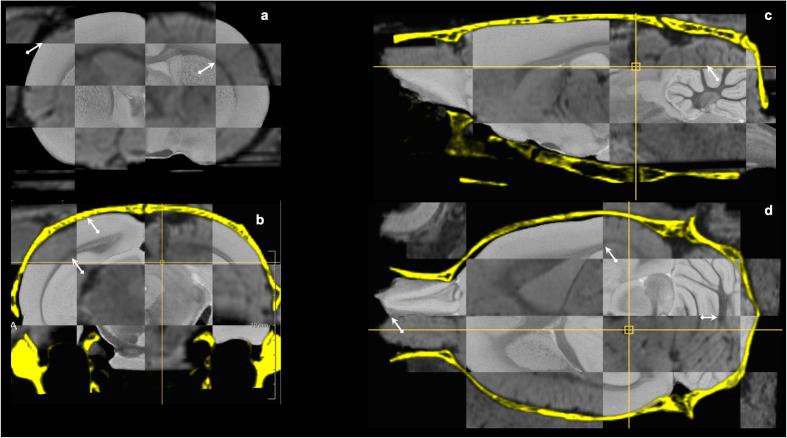

Stereotactic neurosurgery is used in pre-clinical research of neurological and psychiatric disorders in experimental rat and mouse models to engraft a needle or electrode at a pre-defined location in the brain. However, inaccurate targeting may confound the results of such experiments. In contrast to the clinical practice, inaccurate targeting in rodents remains usually unnoticed until assessed by ex vivo end-point histology. We here propose a workflow for in vivo assessment of stereotactic targeting accuracy in small animal studies based on multi-modal post-operative imaging. The surgical trajectory in each individual animal is reconstructed in 3D from the physical implant imaged in post-operative CT and/or its trace as visible in post-operative MRI. By co-registering post-operative images of individual animals to a common stereotaxic template, targeting accuracy is quantified. Two commonly used neuromodulation regions were used as targets. Target localization errors showed not only variability, but also inaccuracy in targeting. Only about 30% of electrodes were within the subnucleus structure that was targeted and a-specific adverse effects were also noted. Shifting from invasive/subjective 2D histology towards objective in vivo 3D imaging-based assessment of targeting accuracy may benefit a more effective use of the experimental data by excluding off-target cases early in the study.

立体定向神经外科用于在实验大鼠和小鼠模型的神经和精神疾病的临床前研究中,将针或电极植入大脑中预先定义的位置。然而,不准确的靶向可能会混淆此类实验的结果。与临床实践不同,在啮齿动物中,不准确的靶向通常不会被注意到,直到通过离体终点组织学进行评估。我们在这里提出了一种基于小动物研究中多模态术后成像的立体定向靶向准确性的体内评估工作流程。从术后 CT 中成像的物理植入物或术后 MRI 中可见的其轨迹,在 3D 中重建每个动物的手术轨迹。通过将个别动物的术后图像配准到共同的立体定向模板,来量化靶向准确性。我们使用了两个常用的神经调节区域作为靶点。目标定位误差不仅具有可变性,而且靶向也不准确。只有大约 30%的电极位于靶向的亚核结构内,并且还注意到了特定的不良反应。从侵入性/主观的 2D 组织学向基于客观的体内 3D 成像靶向准确性评估的转变,可以通过在研究早期排除非目标病例,从而更有效地利用实验数据。